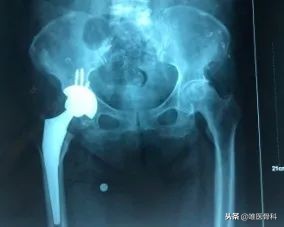

髋关节置换术,简单来说就是换一个关节,之前的髋关节出问题了,无法正常活动,采用人工髋关节置换部分或全部的髋关节,以重建关节运动功能的一种手术。

这种手术方式适用于几乎全部健康状况能够耐受手术的老年人,无论术前是否存在影响关节功能的病变,如股骨头坏死、先天性髋关节发育不良等。它的优势是术后可以早期下地康复训练(术后第一天即可),卧床时间较短,能够避免因卧床导致的相关并发症。

人工髋关节功能良好,基本可恢复至术前的功能状态,被誉为二十一世纪最成功的手术。该术式可能出现脱位,感染等并发症,但随着医疗水平和医疗技术的进步,上述并发症的风险已经非常低(<1%)。

内固定术与髋关节置换术相比,两者术中出血量、手术时间差距不大。对于高龄老人,髋关节置换术术后髋关节功能恢复好、术后卧床时间短、翻修手术率低,它最大的优势就是患者术后可以早期负重,并避免术后股骨头坏死和骨关节炎造成的二次手术。因此在临床上对于能耐受手术的高龄老年患者应首选髋关节置换术。